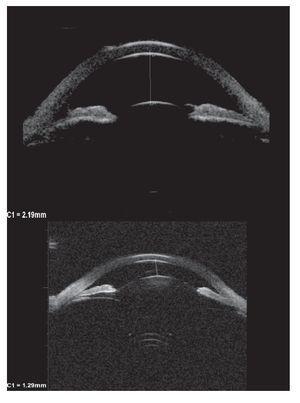

Hombre de 13 años de edad, sin antecedentes heredofamiliares ni personales patológicos de importancia. El motivo de consulta fue la disminución progresiva de la agudeza visual de meses de evolución, acompañado en ocasiones de dolor periocular intermitente. A la exploración física se encontró una talla de 1.52 m, la cual se encuentra dentro de la percentila 50 para la edad, así como una discreta braquidactilia en ambas manos. La exploración oftalmológica reveló: agudeza visual de 20/400 en ambos ojos y una agudeza visual mejor corregida de 20/30 y 20/40 respectivamente, con una refracción de -11.00 = -0.75X145° en OD y -11.00 = -2.50X5° en OI. La posición primaria de la mirada en ortoposición y los movimientos oculares fueron normales. La presión intraocular fue de 26 mmHg en OD y 21 mmHg en OI. El segmento anterior de ambos ojos bajo lámpara de hendidura, mostró una cámara anterior estrecha, tanto en la periferia como en el centro (Figuras 1a y 1b) con un ángulo iridocorneal en ambos ojos de 0 en los 360° (Figuras 2a y 2b). En segmento posterior de ambos ojos encontramos una excavación papilar de aproximadamente 6/10, con un defecto en la capa de fibras nerviosas evidenciada por las fotografías libres de rojo (Figuras 3a y 3b). El paciente fue tratado inicialmente mediante la realización de iridotomías con láser de YAG en ambos ojos y tratamiento tópico con una combinación brimonidina-timolol-dorzolamida, acudiendo nuevamente a consulta dos días posteriores al tratamiento encontrando una presión de 13 mmHg en ambos ojos con las iridotomías permeables (Figura 4).

Se realizaron los siguientes estudios: ultra-biomicroscopía (UBM) antes y después de las iridotomías (Figuras 5a y 5b), en la que se observa cómo hubo un aumento en la amplitud de la cámara anterior en ambos ojos, así como la microesferofaquia (Diámetro ecuatorial OD 7.46 mm y OI 7.67 mm), campos visuales 24-2 (Figuras 6a y 6b), en los que se aprecia reducción generalizada de la sensibilidad, tomografía de coherencia óptica (OCT) de capa de fibras nerviosas (Figura 7), en donde observamos una pérdida de la relación ISNT inferior, superior, nasal y temporal); ecografía en la que se evidencia un eje antero-posterior de 22.45 mm en OD y 22.65 mm en OI. Además, se solicitó interconsulta con el servicio de genética. En la Tabla 1 se muestra la medición del ángulo irido-corneal antes y después de las iridotomías en los diferentes meridianos, así como de la cámara anterior.

¿ Figura 5a. OD. UBM. Antes y después de iridotomías.

¿ Figura 5b. OI. UBM. Antes y después de iridotomías.